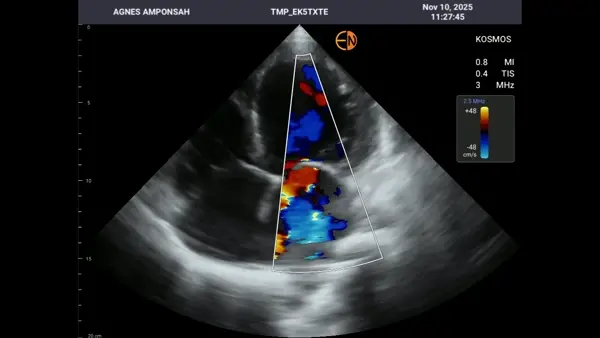

A 47-year-old woman with obesity, hypertension, dyslipidemia, and a history of chronic heart failure presented with shortness of breath, peripheral edema, and clinical signs of deterioration. Without on-site echocardiography, her worsening status could not be objectively assessed. A bedside AISAP exam revealed EF 14%, severe mitral regurgitation, and severe tricuspid regurgitation, confirming significant decline from her prior evaluation. In this low-resource setting, AISAP provided the essential diagnostic clarity needed to guide timely management during an acute heart failure exacerbation.